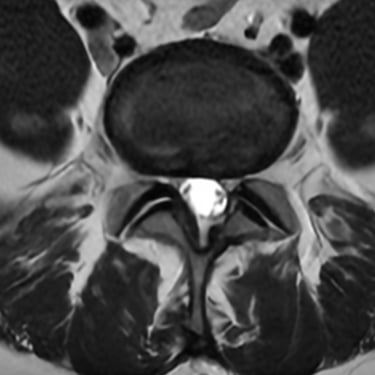

La discopatía degenerativa lumbar es una de las principales causas de dolor lumbar crónico. Se caracteriza por la pérdida de altura discal, deshidratación y cambios en las superficies vertebrales adyacentes. En la resonancia magnética (RMN) se identifican los cambios Modic, que reflejan alteraciones inflamatorias y degenerativas en el hueso subcondral: tipo I (edema), tipo II (grasa) y tipo III (esclerosis). Estos hallazgos permiten correlacionar el dolor lumbar con la patología discal y orientar un tratamiento personalizado. La RMN es, por tanto, una herramienta esencial para el diagnóstico preciso y la planificación terapéutica en pacientes con esta condición.